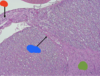

3

Q

A

Blue –> nucleus

Black –> Dendrite

Yellow –> axon hillock

Red –> axon hillock

How well did you know this?